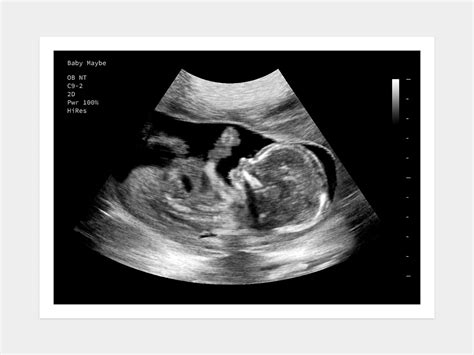

You may also have a 16 weeks pregnant ultrasound at your appointment, but don’t be alarmed if you don’t, as your OB will do one closer to mid-pregnancy. View all At a 16-week pregnancy scan, you’ll see your baby’s development and check for any potential issues, ensuring a healthy pregnancy journey. A 16-week pregnancy scan, also known as a mid-pregnancy ultrasound or anomaly scan, is an essential part of prenatal care. Find out what to expect from your 16-weekultrasound during your pregnancy, including the development of your baby and what the scan can reveal.

Is a 16-weekultrasound typical? Understand the standard prenatal scan schedule, specific reasons for an early check, and what can be assessed at this stage. · As usual, you’ll likely have a urine test; your OB will be checking your urine for signs of gestational diabetes and preeclampsia. You may also have a 16 weeks pregnant ultrasound at your appointment, but don’t be alarmed if you don’t, as your OB will do one closer to mid-pregnancy.

At a 16-week pregnancy scan, you’ll see your baby’s development and check for any potential issues, ensuring a healthy pregnancy journey. A 16-week pregnancy scan, also known as a mid-pregnancy ultrasound or anomaly scan, is an essential part of prenatal care. Find out what to expect from your 16-weekultrasound during your pregnancy, including the development of your baby and what the scan can reveal. What to expect while getting ready for a 16 weekultrasound? Read a complete guide to learn about the purpose and procedure, and prepare for what you will see. · Ultrasounds help track your baby's growth and spot any issues early.

Most people have a few key ultrasounds, but certain conditions may require more. Safety is a top priority, so ultrasounds... Is a 16-weekultrasound typical? Understand the standard prenatal scan schedule, specific reasons for an early check, and what can be assessed at this stage. Discover what to expect during a 16-weekultrasound scan. Learn about baby development and gender determination at this exciting stage of pregnancy. • What are ultrasounds in pregnancy?• Why do I need a 16-weekultrasound?• What does a 16-weekultrasound look like? 16Weeks What to Expect | 16weekUltrasound. Diana In The Pink. 698K views • 4 years ago. 16Weeks Pregnant Ultrasound - Baby Gender Reveal.16weekultrasound | 17 weeks pregnant ultrasound, Ultrasound prank, Ultrasound pictures. Discover what happens during the 16-weekultrasound, how your baby is developing, and why this scan is an important milestone in pregnancy care. At week 16 your belly will be growing pretty fast. During The 16WeekUltrasound. This ultrasound will be carried out the same way as your first. Pregnancy work-up included a traditional 22-weekultrasound scan, an echocardiography, and the option of a 10-gene Rasopathy panel after a normal 16-week scan. Why Should Pregnant Women Have an Ultrasound at 16Week? Things start to get a bit exciting once you hit the 16-week mark and ultrasound is important to understand your baby’s progress.